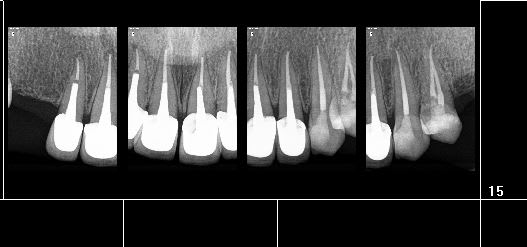

Capture d  cran 2015 03 12 12.28 - Eugenol